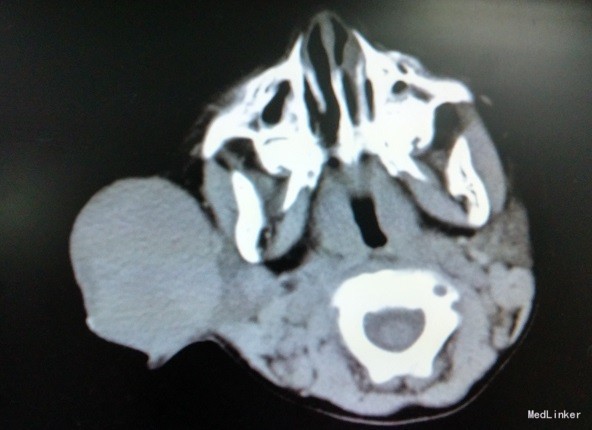

主诉:男,3岁,确诊“横纹肌肉瘤”7月,拟化疗 病史:入院前7月患儿因右耳前包块于我院行细针穿刺活检术,术后免疫组化提示胚胎型(间变型)横纹肌肉瘤。术后于我院就诊,完善胸部增强CT、腹部彩超、浅表淋巴结超声、骨髓涂片等检查后诊断为横纹肌肉瘤(胚胎型,间变型,Ⅰ型),首次予以IVA方案化疗。后于我院规律化疗,右耳前包块较前有所缩小。3月前行“右面部横纹肌肉瘤扩大切除术+右腮腺部分切除术+右颈部轴形瓣转移修复术”术中冰冻切片提示边界均未见肿瘤细胞,术后病理检查支持横纹肌肉瘤诊断,FISH未检出有意义的FOX1(FKHR)基因易位。末次按IVA方案给予异环磷酰胺、长春地辛、更生霉素化疗。现患儿一般情况可,无发热、咳嗽、呕吐、腹泻等不适,拟化疗入院。末次化疗以来,体重增加1Kg。

查体:右侧耳前可见一长约4cm手术切口瘢痕,愈合良好。 辅检:血常规:WBC 12.3×109/L 、N:11.96×109/L,Hb90g/L,PLT42*10^9;CRP:130mg/L,心电图示:窦性心律不齐,电轴左偏-1°,心电图大致正常。血培养示:粘质沙雷菌、产酸克雷伯菌,对亚胺培南敏感。

诊断:横纹肌肉瘤(胚胎型,间变型,Ⅰ型) 处理:异环磷酰胺、长春地辛、放线菌素D化疗,辅以水化碱化、止吐、美司钠,复合辅酶护心、护肝,止血敏改善血小板功能,泰能抗感染,丙球支持等。